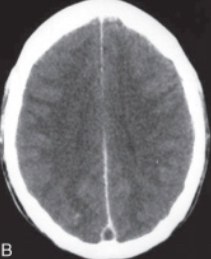

Question 6 - Interprétez l'imagerie cérébrale

Il s’agit d’un scanner cérébral injecté qui met en évidence un défaut d’opacification par le produit de contraste du sinus longitudinal supérieur. Ce signe appelé signe du delta traduit la présence d’un thrombus au sein du sinus. Les sténoses bilatérales des sinus transverses sont des signes indirects et non spécifiques que l’on retrouve dans les hypertensions intracrâniennes chroniques idiopathiques.